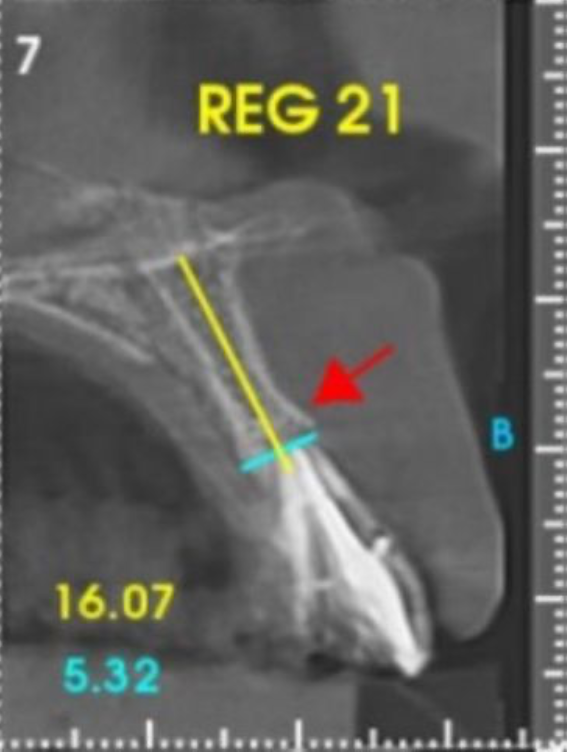

O planejamento do tratamento deve envolver uma avaliação abrangente da saúde bucal do paciente, incluindo a avaliação da densidade óssea e a disponibilidade de osso adequado para a estabilidade do implante. A colocação do implante em um posicionamento tridimensional perfeito e a estabilidade primária adequada são essenciais para o sucesso a longo prazo.

Conforme discutido na literatura, a colocação imediata de implantes na zona estética requer que o clínico tenha conhecimento e experiência em diversas áreas. Isso inclui diagnóstico estético, técnicas de extração minimamente invasivas, procedimentos cirúrgicos plásticos orais (por exemplo, enxerto de tecidos duros e moles) e colocação de implantes tridimensionais (3D) precisos com o uso de um implante mais estreito (3,3 mm a 4,3 mm), o que garante um espaço vestibular de pelo menos 2 a 3 mm adjacente à parede do alvéolo bucal intacto. Isso pode ser pré-planejado com uma análise cuidadosa através de exames de imagem para uma melhor compreensão do plano restaurador. O uso de técnicas avançadas de imagem, como a tomografia computadorizada de feixe cônico (CBCT), pode auxiliar no planejamento preciso do tratamento e na colocação do implante.